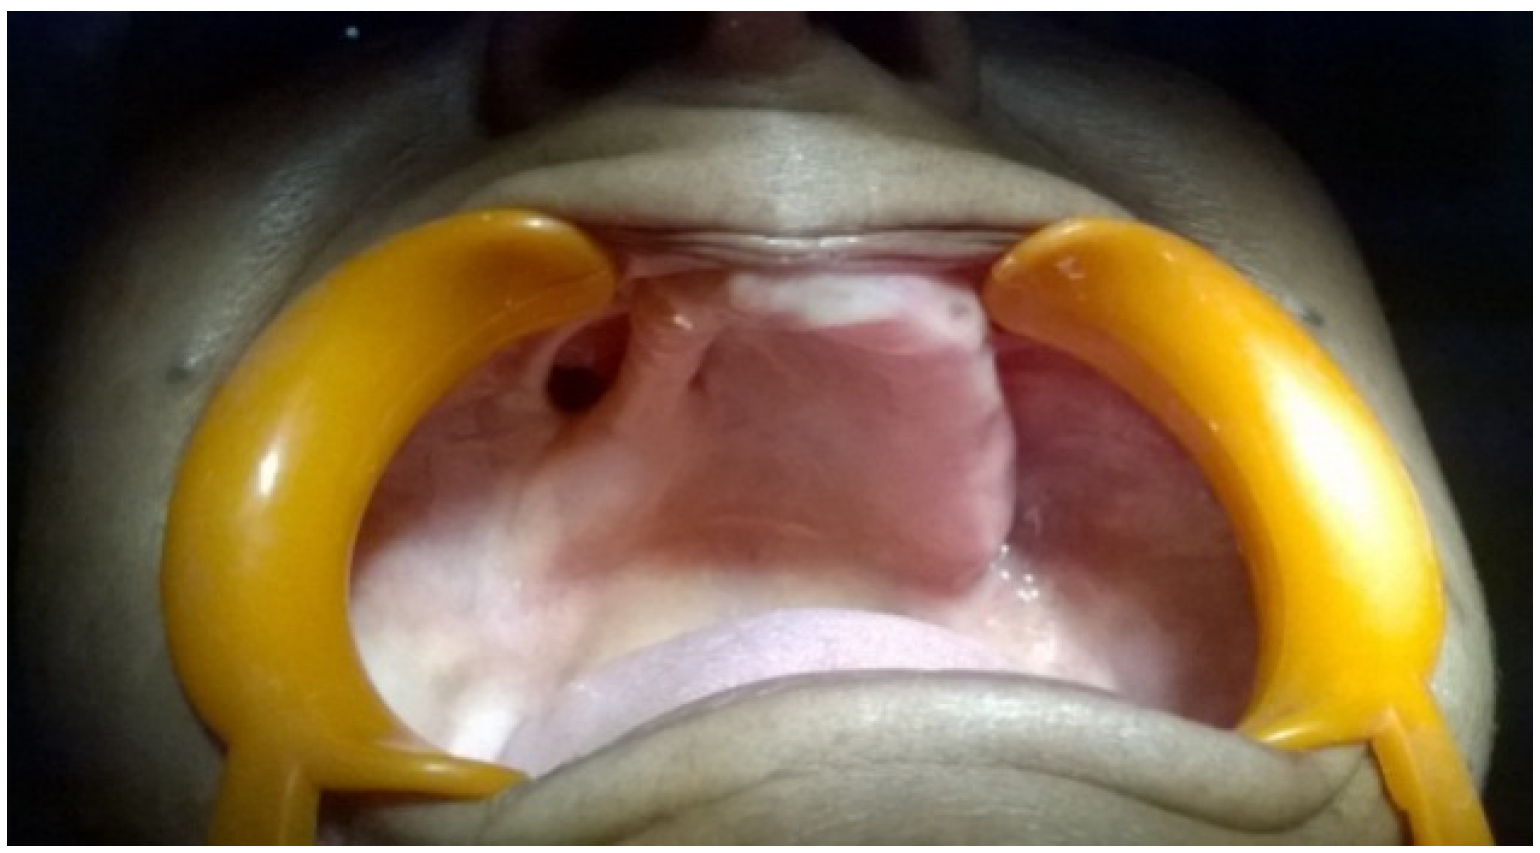

2. Case Presentation

3. Discussion